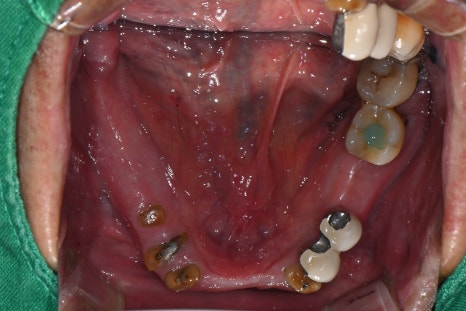

After lower jaw insurance-covered implant placement

After full extraction of the upper teeth one month later

- Upper jaw treatment: complete denture fabrication after extraction

After extracting the unstable teeth, the gums were allowed to stabilize,

and impressions were taken to newly fabricate an upper complete denture.

- Lower jaw treatment: insurance-covered implants + partial denture

Two insurance-covered implants were placed in the lower jaw.

After confirming that the implants had integrated well with the gums,

an insurance-covered partial denture using implant attachments was fabricated.

It was secured much more stably than before, and the feeling of a foreign body was greatly reduced.